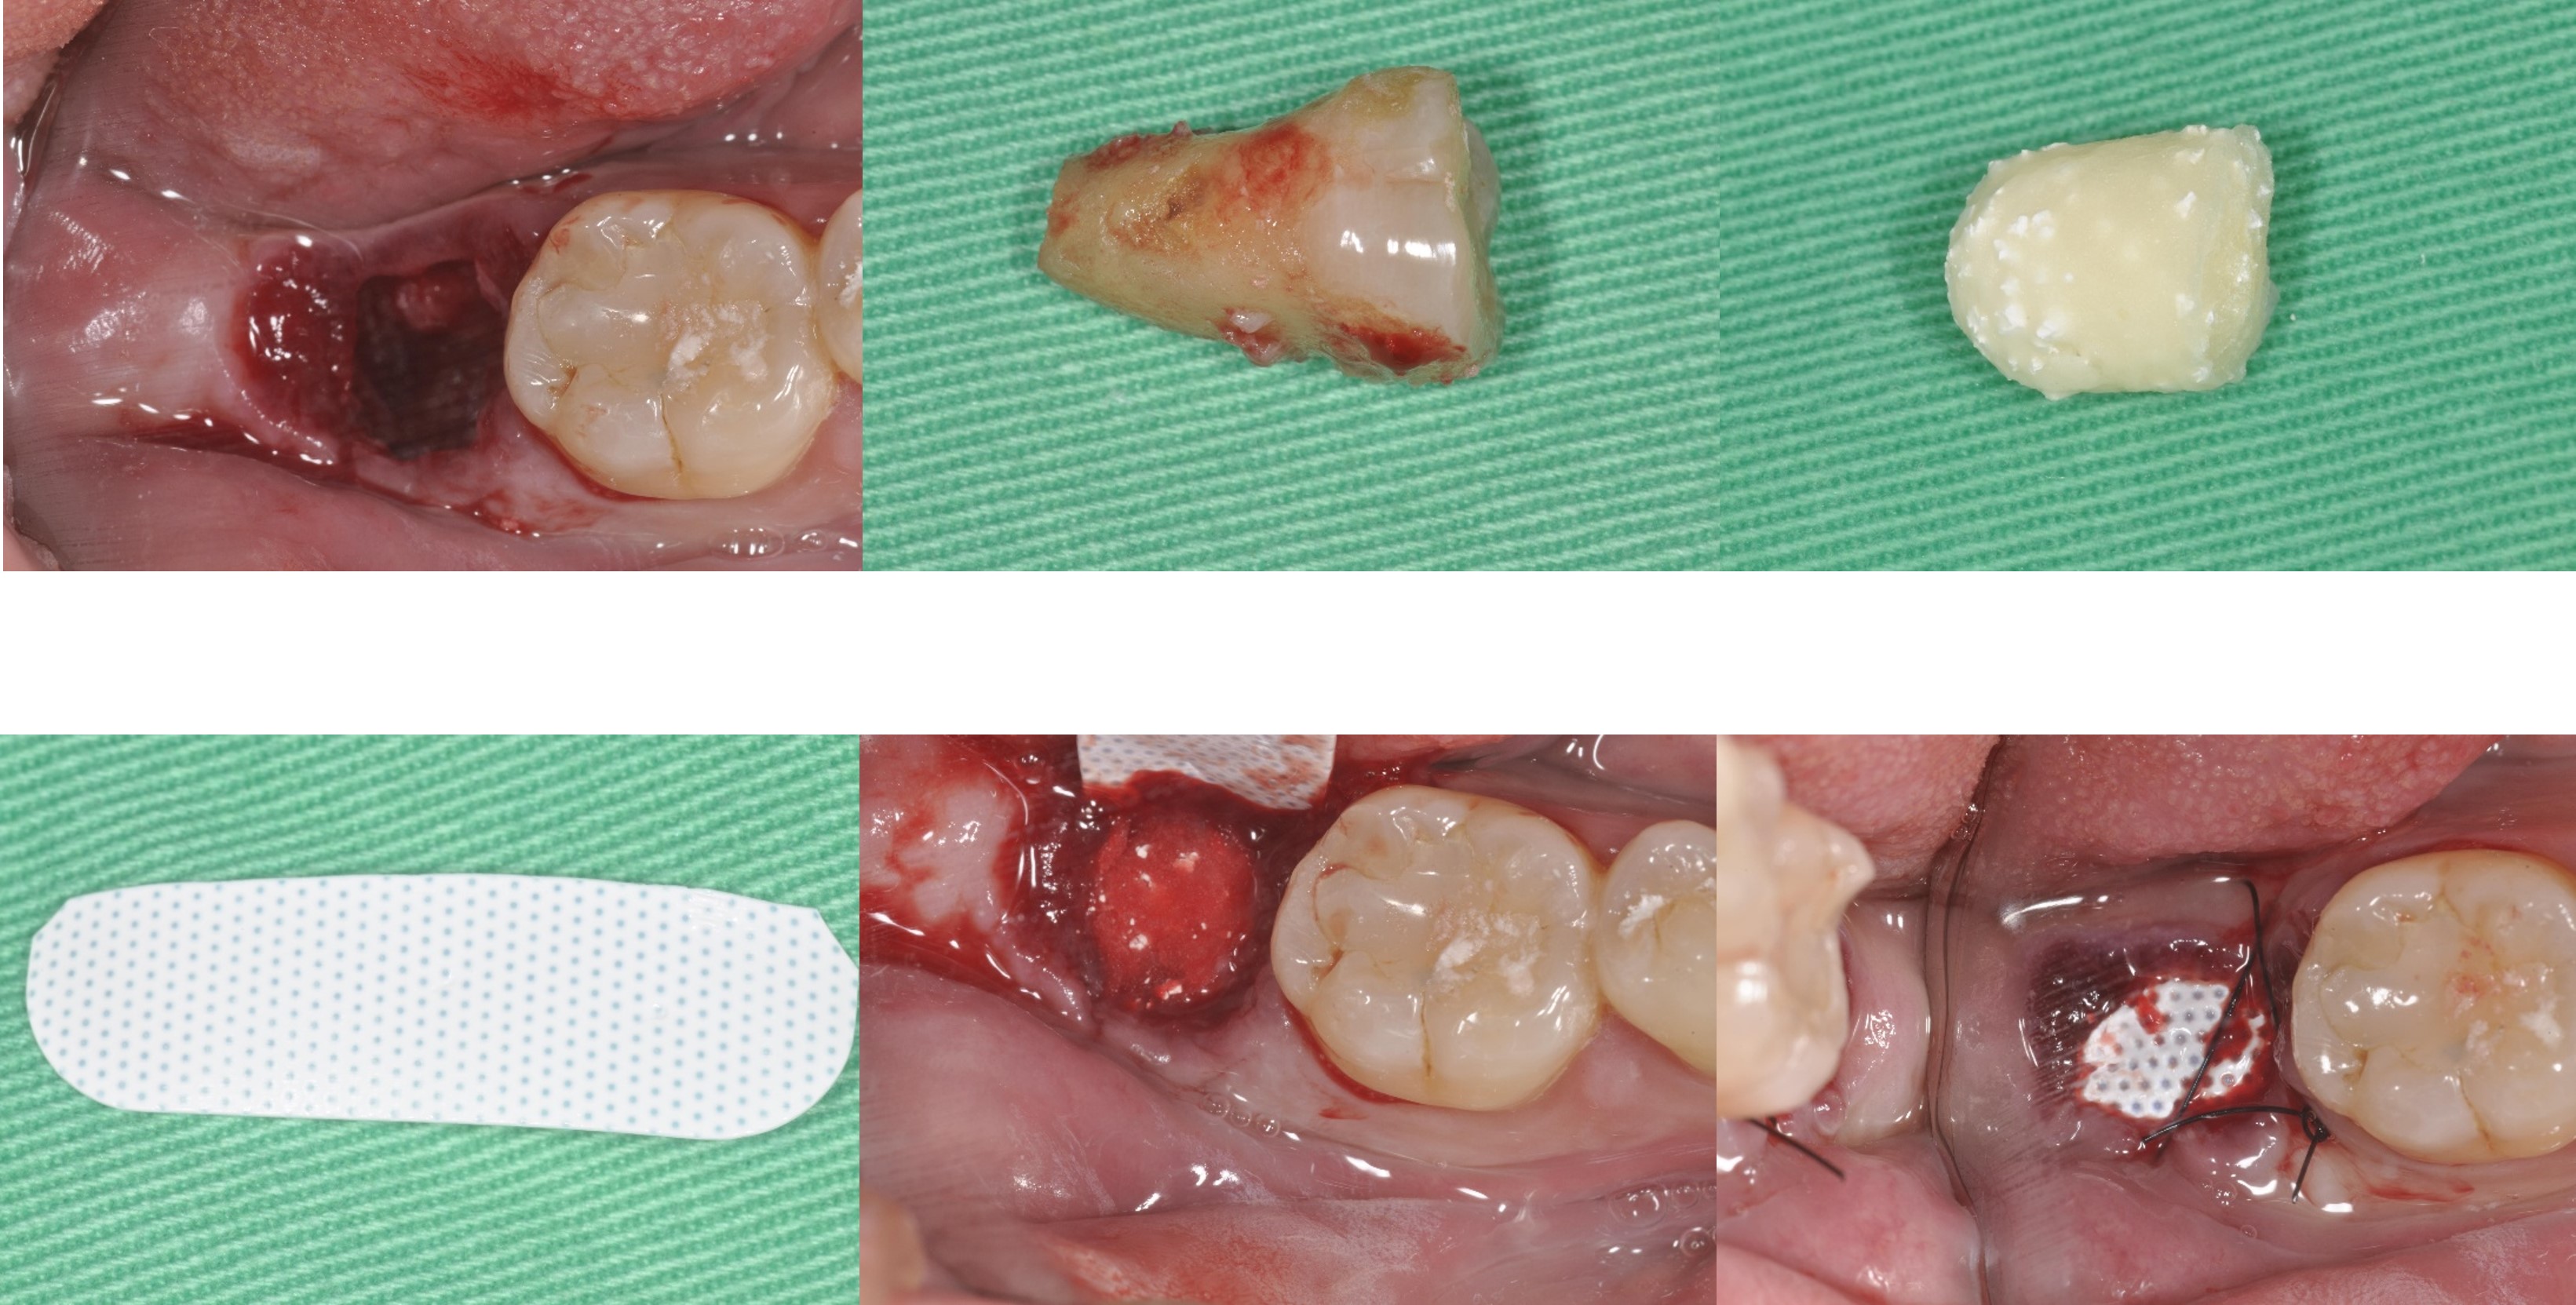

拔牙後進行骨脊保存術